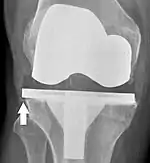

Loosening of the prosthesis can be indicated on X-ray by thin radiolucent spaces around the implant, or more obviously by implant displacement.[54]

Knee replacement is routinely evaluated by X-ray, including the following measures:

HKA: Hip-knee-ankle angle, which is ideally between 3° varum to 3° valgum from a right angle.[60]

- FFC: frontal femoral component angle. It is typically regarded as optimal when being 2–7° in valgus.[61]

- FTC: frontal tibial component angle, which is regarded as optimal when being at a right angle. A varus position of more than 3° has generally been found to increase the failure rate of the prosthesis.[61]

- Anterior femoral notching (the femoral component causing reduced thickness of the distal femur anteriorly), seems to cause an increased risk of fractures when exceeding about 3 mm.[62]

- LTC: lateral (or sagittal) tibial component angle, which is ideally positioned so that the tibia is 0–7° flexed compared to at a right angle with the tibial plate.[61]